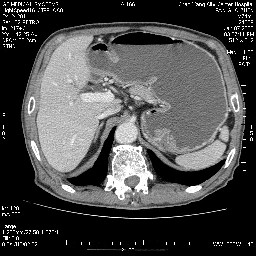

女,74岁,呕吐10余日

壶腹部的占位性病变,考虑为十二指肠癌并梗阻,但脾内多发性低密度区为转移吗?

还有胃、脾之间可见有侧支循环建立。左肾盂积水。

肝胰壶腹占位,考虑-壶腹癌!

胃体部粘膜不规则增厚,胃肠造影也显示充盈缺损-胃溃疡?胃癌?

双肾多发小囊肿;左肾积水。

十二指肠降段扩张,水平段狭窄成鼠尾状,肠壁明显增厚,胰腺勾突增大成不均匀强化,其内可见低密度区,胆囊增大,1十二指肠水平段腺癌侵犯胰腺勾突可能大,2胰腺癌侵犯十二指肠(只有胆囊增大没有肝内外胆管扩张不好解释)代除外.

十二指肠降段扩张,水平段狭窄成鼠尾状,肠壁明显增厚,胰腺勾突增大成不均匀强化,其内可见低密度区,胆囊增大,1十二指肠水平段腺癌侵犯胰腺勾突可能大,2胰腺癌侵犯十二指肠 。